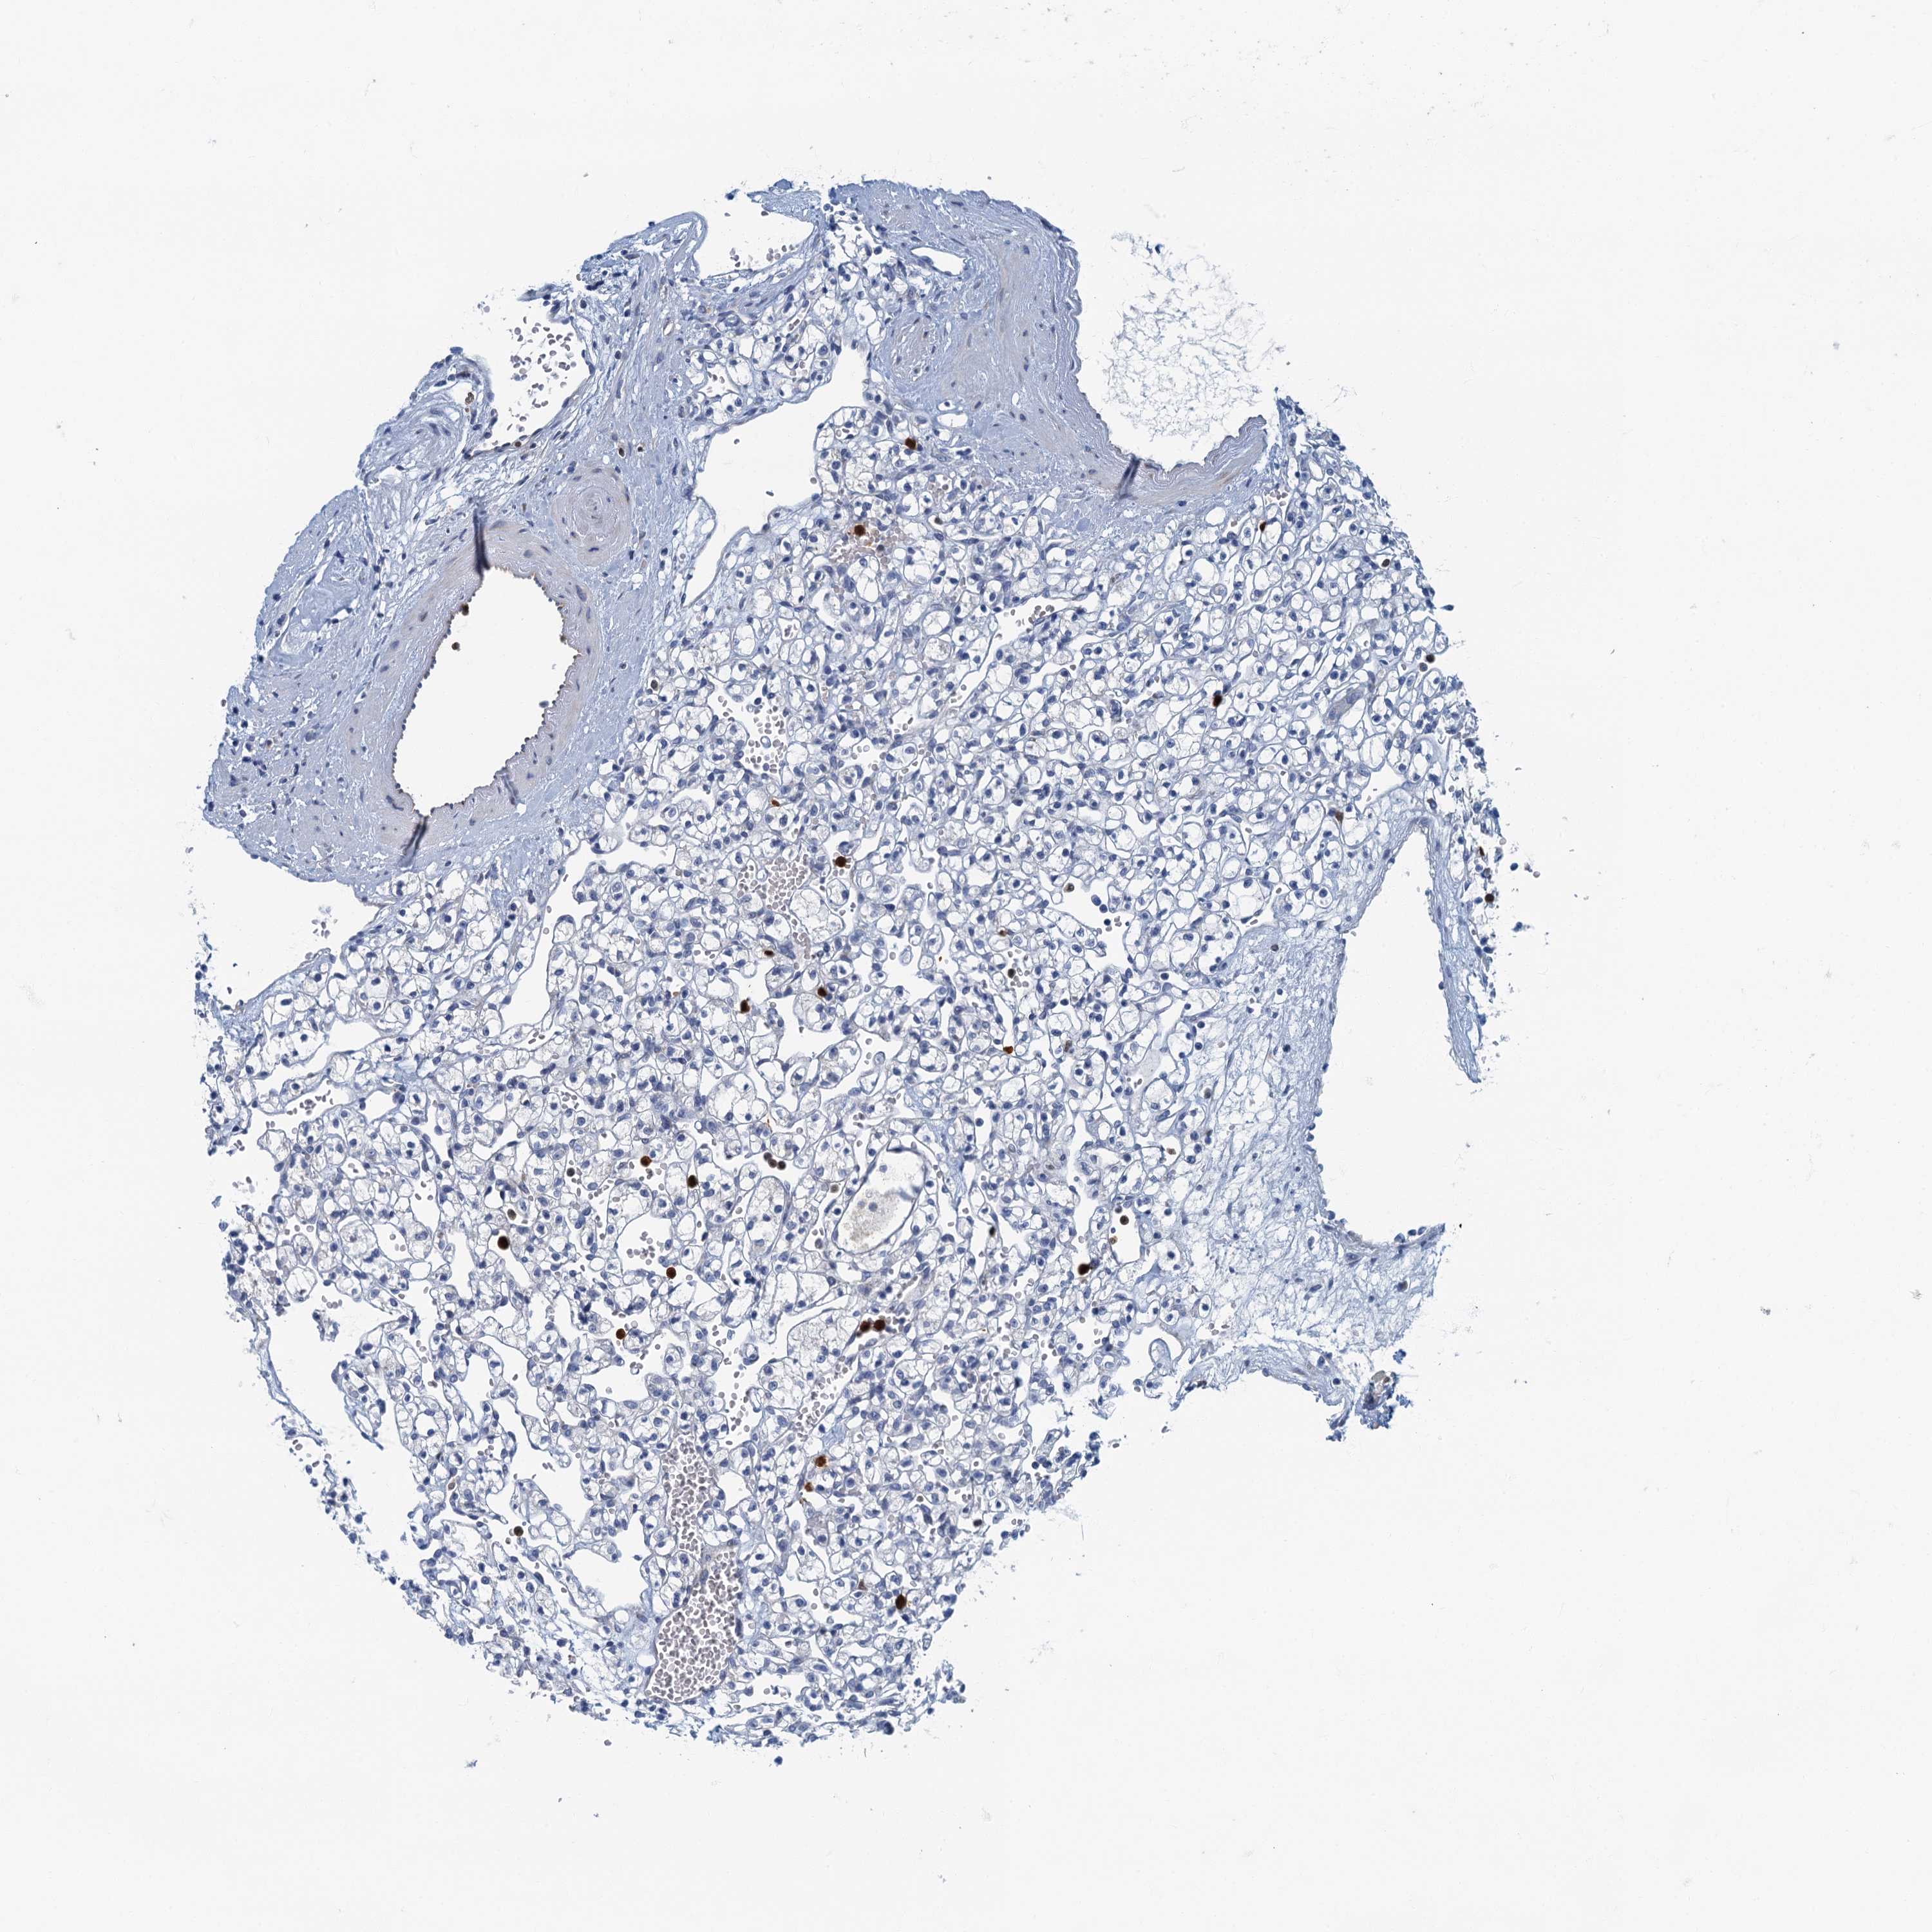

KIDNEY RENAL CLEAR CELL CARCINOMA (VALIDATION) - Interactive survival scatter ploti

The Survival Scatter plot shows the clinical status (i.e. dead or alive) for all individuals in the patient cohort, based on the same data that underlies the corresponding Kaplan-Meier plots. Patients that are alive at last time for follow-up are shown in blue and patients who have died during the study are shown in red.

The x-axis shows the expression levels (FPKM) of the investigated gene in the tumor tissue at the time of diagnosis. The y-axis shows the follow-up time after diagnosis (years). Both axes are complimented with kernel density curves demonstrating the data density over the axes. The top density plot shows the expression levels (FPKM) distribution among dead (red) and alive patients (blue). The right density plot shows the data density of the survived years of dead patients with high and low expression levels respectively, stratified using the cutoff indicated by the vertical dashed line through the Survival Scatter plot. This cutoff is automatically defined based on the FPKM cutoff that minimizes the p-score. The cutoff can be changed by dragging the vertical line or by entering a cutoff value in the square labeled "Current cut-off".

Under the Survival Scatter plot the p-score landscape (black curve; left axis) is shown together with dead median separation (red curve; right axis). Dead median separation is the difference in median mRNA expression between patients who have died with high and low expression, respectively. It is calculated as follows: median FPKM expression of dead patients with high expression - median FPKM expression of dead patients with low expression. This is intended to aid the user in visually exploring custom cutoffs and the associated p-scores and dead median separation.

Individual patient data is displayed and can be filtered by clicking on one or more of the category buttons on the top of the page. Categories describing expression level and patient information include: high, low, alive, dead, female, male and tumor stages. The scale of the x-axis can be toggled between linear and log-scale by clicking on the "x log" button. Mouse-over function shows TCGA ID, patient information and mRNA expression (FPKM) for each patient.

& Survival analysisi

Kaplan-Meier plots summarize results from analysis of correlation between mRNA expression level and patient survival. Patients were divided based on level of expression into one of the two groups "low" (under cut off) or "high" (over cut off). X-axis shows time for survival (years) and y-axis shows the probability of survival, where 1.0 corresponds to 100 percent.

ANKDD1A is not prognostic in Kidney Renal Clear Cell Carcinoma (validation)

Best expression cut offi

Based on the FPKM value of each gene, patients were classified into two groups and association between prognosis (survival) and gene expression (FPKM) was examined. The best expression cut-off refers the FPKM value that yields maximal difference with regard to survival between the two groups at the lowest log-rank P-value. Best expression cut-off was selected based on survival analysis .

When clicking on this number, the vertical dashed line indicating cut-off, the interactive survival plot, and the Kaplan-Meier curve will be adjusted to show results based on the best expression cut-off.

: 2.3

TCGA RNA samplesi

RNA-seq data is reported as average FPKM (number Fragments Per Kilobase of exon per Million reads), generated by the The Cancer Genome Atlas (TCGA) .

Normal distribution across the dataset is visualized with box plots, shown as median and 25th and 75th percentiles. Points are displayed as outliers if they are above or below 1.5 times the interquartile range. FPKM values of the individual samples are presented next to the box plot.

Average pTPM 2.5

Number of samples 100